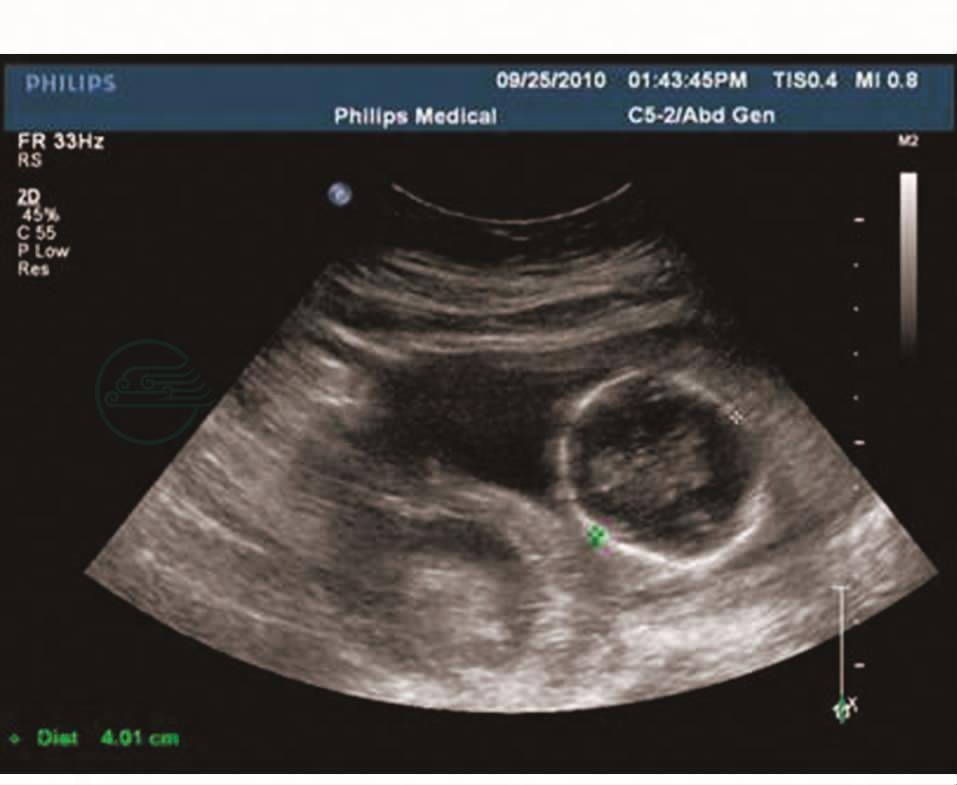

盆腔彩超(2010-09-25):双顶径4.0cm,股骨长2.2cm,羊水深4.1cm,胎盘成熟度0级,厚约1.5cm。母体右附件区见10.4cm×6.0cm×5.5cm包块,边界模糊,形态不规整,内呈中低混合回声伴不规则液性区。提示:1.中期妊娠,单胎,头位,胎儿脐带绕颈;2.母体右附件区包块(图1、图2)。

图1 盆腔彩超